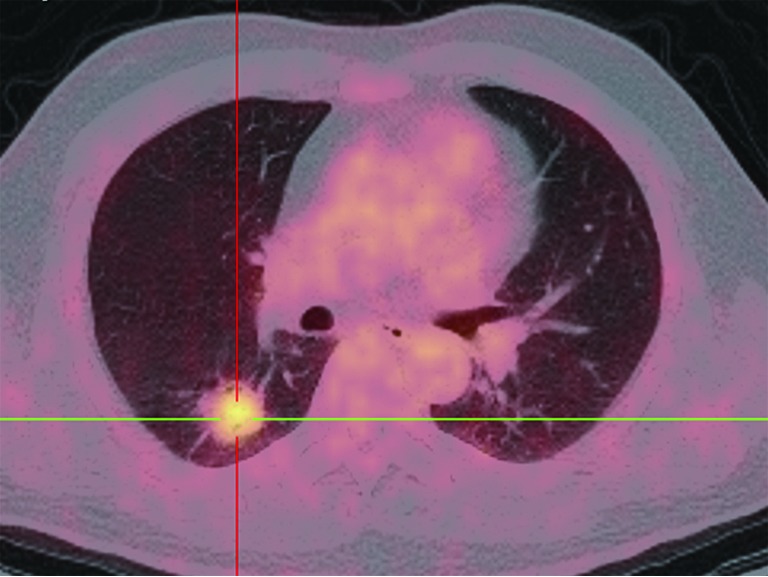

Figure 11.

PET-CT shows a case of adenocarcinoma with a SUVmax of 4.14.